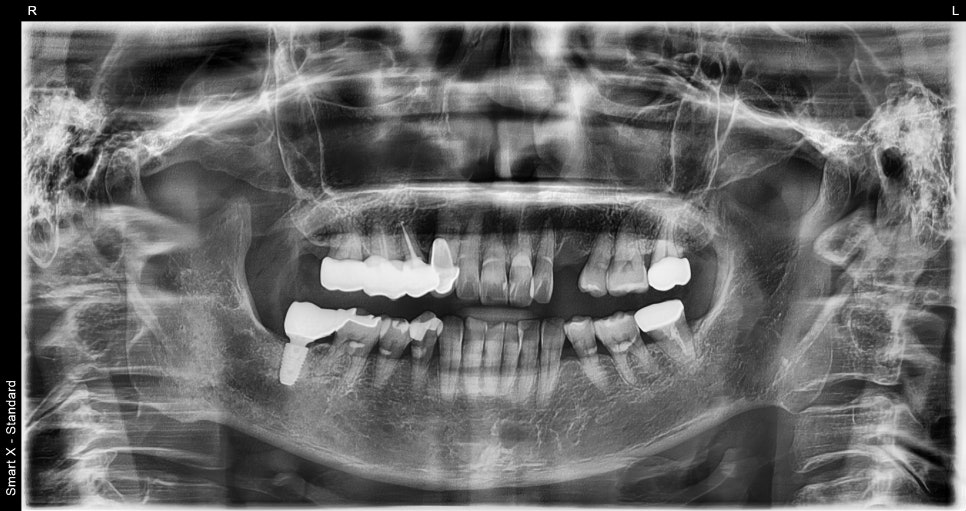

📸 파노라마 엑스레이

골수염(Osteomyelitis) 환자분 초진 엑스레이